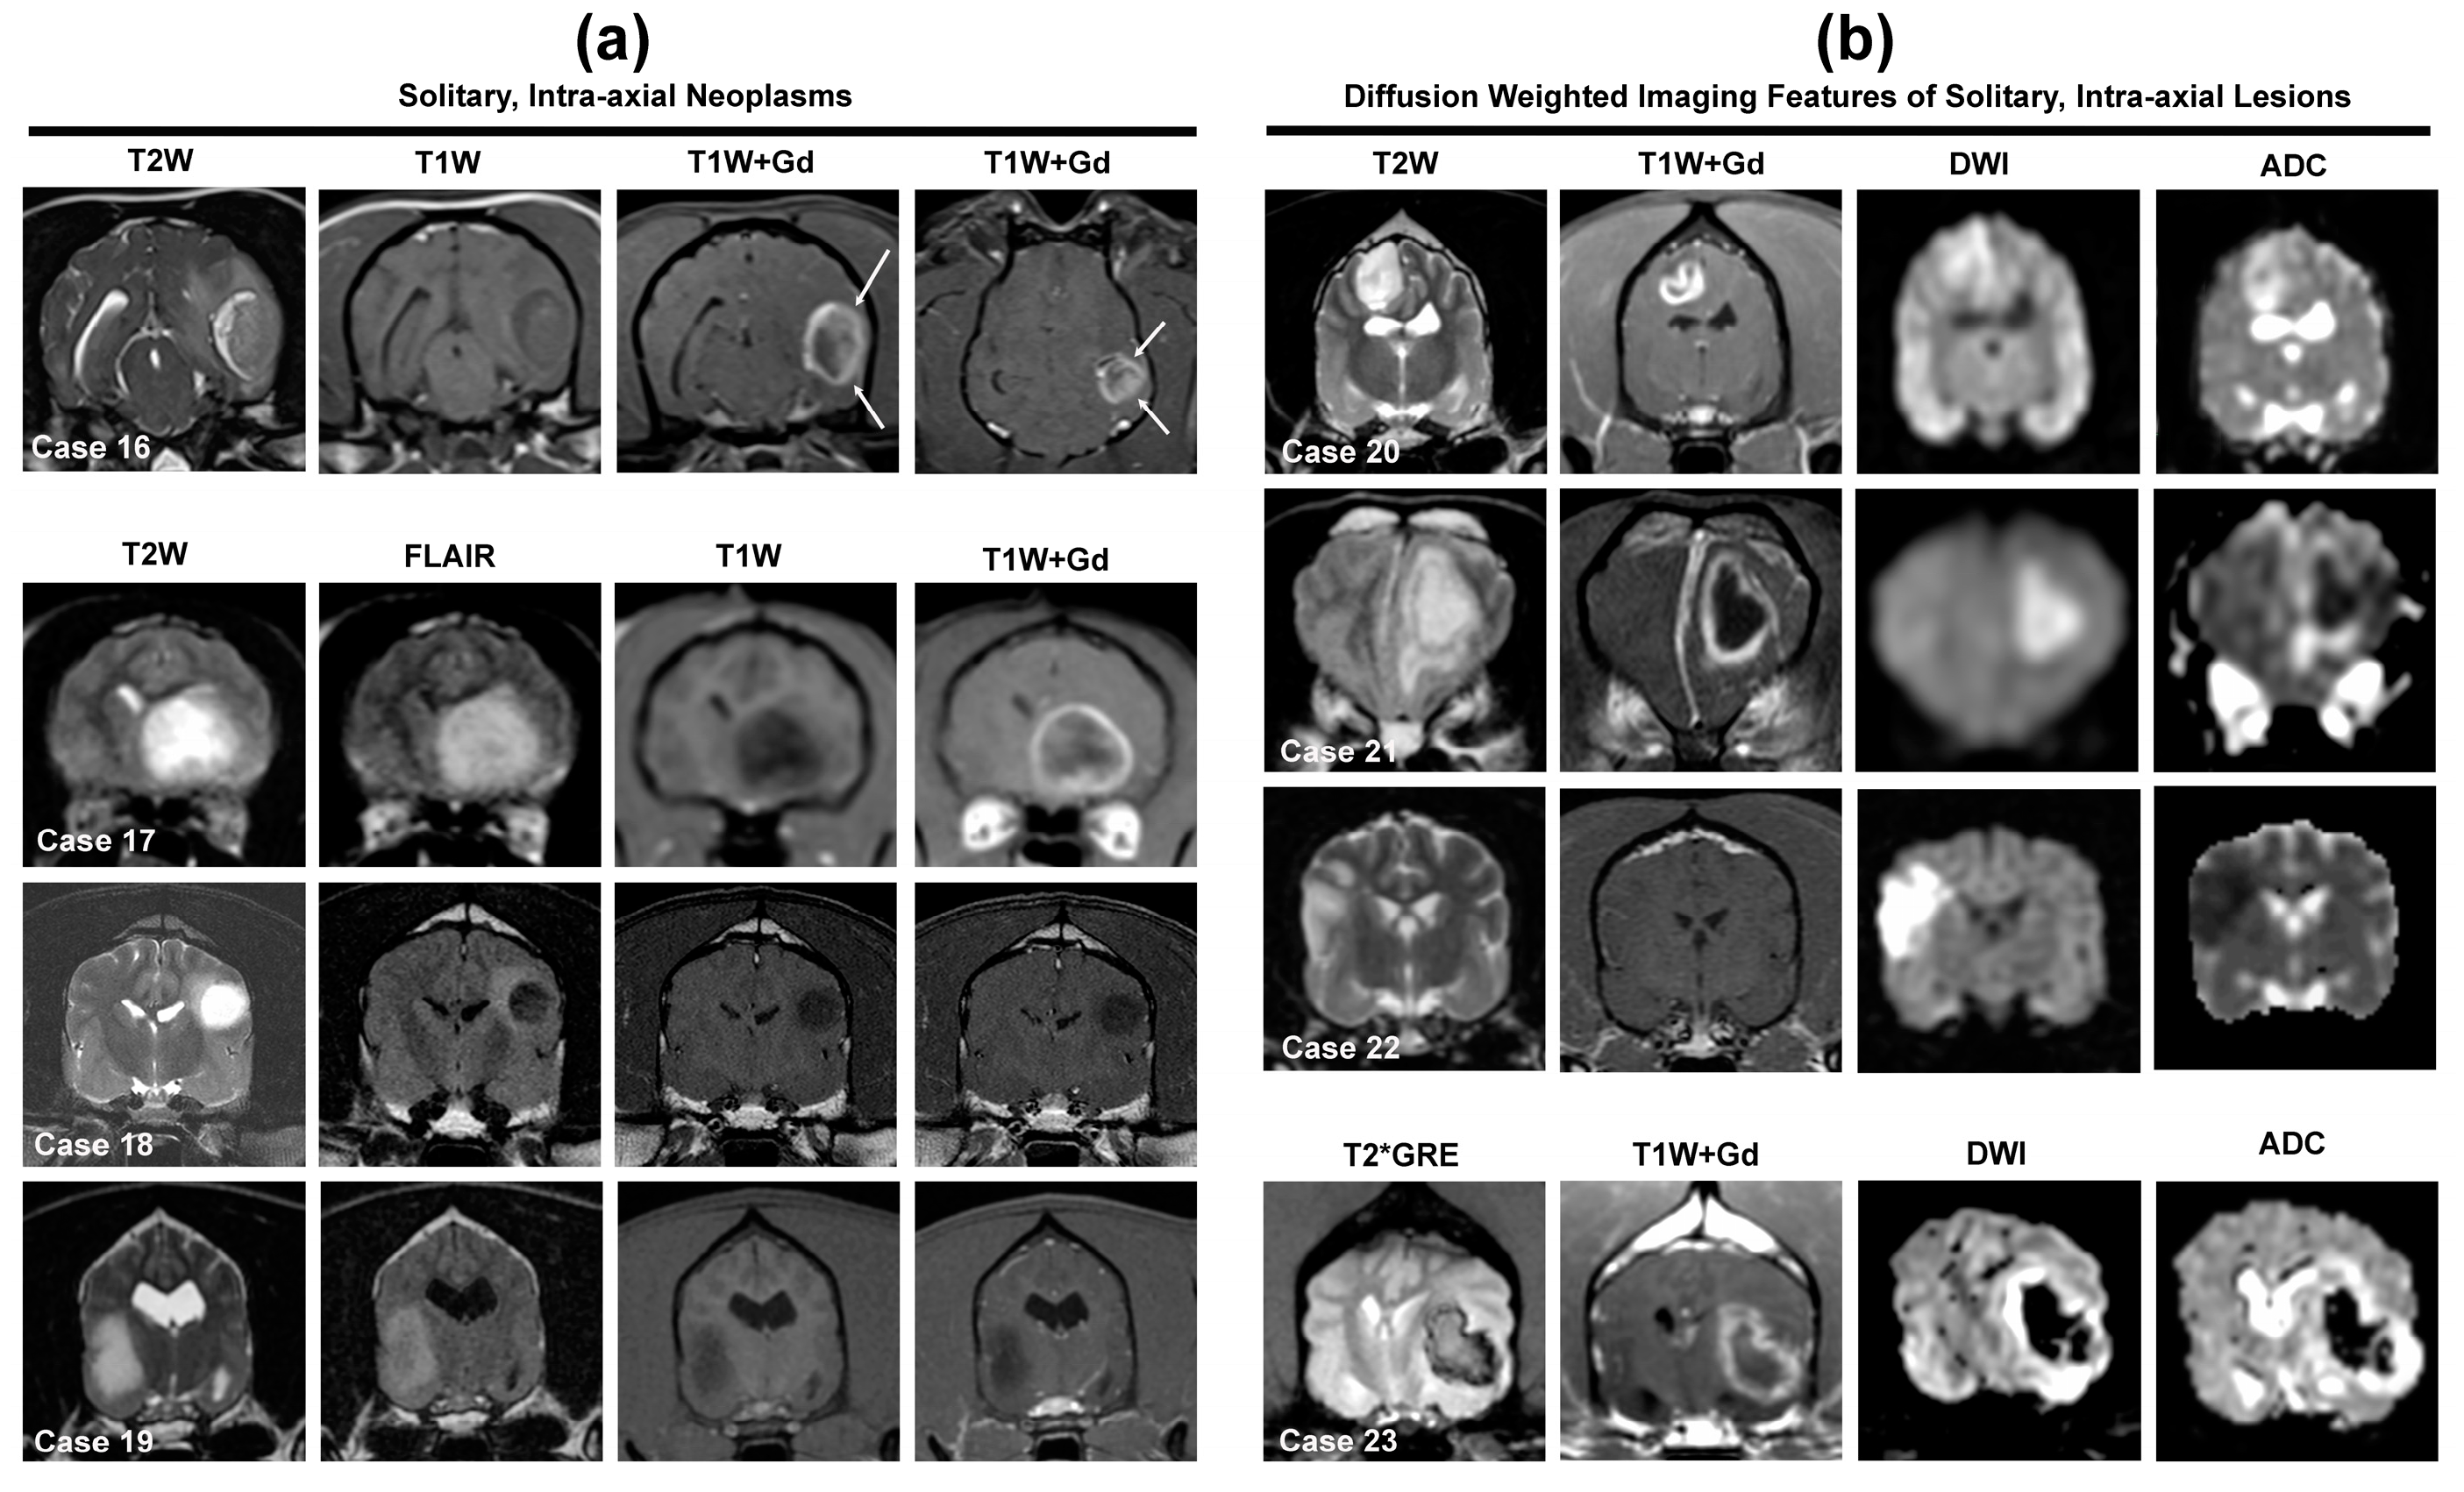

Figure 5.

MRI features of solitary intra-axial gliomas of dogs and cats (a) and diffusion-weighted imaging appearances of solitary intra-axial lesions that can mimic neoplasms (b). Case 16—canine high-grade, ring-enhancing oligodendroglioma in the temporal and piriform lobes demonstrating the ‘claw-sign’ (arrows), mass effect, transtentorial herniation, and peritumoral edema. Case 17—feline diencephalic high-grade oligodendroglioma. The tumor is heterogeneously T2W/FLAIR hyperintense, T1W hypointense, and ring-enhancing. Case 18—canine low-grade, non-enhancing oligodendroglioma in the parietal lobe displaying the T2-FLAIR mismatch sign. Case 19—canine low-grade, T2W/FLAIR hyperintense, T1W hypointense, non-enhancing astrocytoma in the temporal piriform lobe. Case 20—canine high-grade, contrast-enhancing astrocytoma in the parietal lobe, which demonstrates non-uniform, ring-type enhancement and unrestricted diffusion, manifested as lesion hyperintensity on DWI and ADC images (T2W shine-through). Case 21—canine brain abscess with restricted diffusion (DWI hyperintense and ADC hypointense). Note the rim of T2W hypointensity surrounding the central T2W hyperintense lesion, uniform ring-enhancement of the abscess, and regional meningeal enhancement. Case 22—canine middle cerebral arterial ischemic infarction with restricted diffusion. The lesion is restricted to the cerebrocortical gray matter, is not associated with mass effect, and the parenchymal lesion is non-enhancing. Case 23—canine hemorrhagic brain infarction. The infarct is heterogeneously iso-to hypointense on T2*GRE, is ring-enhancing, associated with significant mass effect, and demonstrates T2W blackout (lesion hypointensity on DWI and ADC) due to susceptibility effects of hemorrhage. On DWI and ADC images, the peripheral hyperintensity surrounding the hypointense lesion core represents perilesional edema.

The primary neoplastic differential diagnostic considerations for solitary intra-axial masses are neuroepithelial tumors, among which oligodendrogliomas and astrocytomas (i.e., gliomas) predominate in the dog (Figure 5, Cases 16–20), with other uncommon to rare possible differentials including undefined glioma (oligoastrocytoma), brain metastasis, ependymoma, lymphoma, HS, and embryonal tumors [2,9,10,31,32,55,66,67,68,69,70,71,72,73,74,75,76,77,78,79,80]. Gliomas can have wide-ranging MRI appearances, resulting in imaging features that may overlap substantially with brain abscesses, ischemic and hemorrhagic brain infarctions, fungal granulomas, immune-mediated encephalitides, leukoencephalopathies, and meningioma [2,6,7,8,10,12,13,14,67,77,78]. The routine inclusion of DWI or DTI sequences in multiparametric MRI imaging protocols is recommended to improve the ability to discriminate neoplastic from non-neoplastic intra-axial masses [6,7,8]. When generating a list of differential diagnoses for solitary intra-axial mass lesions, identifying the lesion T2W signal and diffusion pattern (non-restricted versus restricted) on DWI can facilitate this process (Figure 2 and Figure 5).

Neoplasms, granulomas, and meningoencephalitides are not usually associated with restricted diffusion and typically demonstrate lesion hyperintensity on T2W, DWI, and ADC images (Figure 5, Case 20), a DWI phenomenon termed T2 shine-through [6,8,35,37,66]. However, in the presence of vasogenic edema, these diseases may demonstrate T2 wash out, which appears as lesion hyperintensity on T2W and ADC images, but lesion isointensity on DWI. Restricted diffusion, characterized by lesion hyperintensity on T2W and DWI images corresponding to areas of hypointensity on ADC images, is a hallmark feature of pyogenic abscesses and brain infarctions (Figure 5, Cases 21 and 22) [6,8]. A T2 blackout pattern, which appears as lesion hypointensity in T2W, DWI, and ADC sequences, may be seen in hemorrhagic brain infarctions and tumors containing substantial intratumoral hemorrhage (Figure 5, Case 23).

3.3.1. Gliomas (Astrocytoma, Oligodendroglioma, Undefined Glioma)

The inherent MRI features and signal intensities for gliomas are generally non-specific for neoplasia or for individual tumor type or grade [6,7,8,11,70,74,77,78,79,80]. The majority of gliomas have been documented in the forebrain, although gliomas of any type may occur anywhere in the brain parenchyma [2,70,74,77,78,79,80], and 60–89% of canine gliomas are high-grade tumors [66,69,70,77,78,80]. Gliomas, as well as other intra-axial neoplasms, are often T1W hypo- to isointense and T2W/FLAIR hyperintense (Figure 5a), but heteregeneous signal intensities are common [2,7,8,9,10,11,31,32,70,71,77,78].

Signal heterogeneity may arise from the presence of intratumoral cysts or hemorrhage, which occur in 30–80% and 25–50% of canine gliomas, respectively [2,10,66,69,70,74,77,78,79,80]. Some degree of mass effect and peritumoral edema are features present in ~90% of gliomas [2,7,8,9,10,11,66,69,70,74,77,78,79,80]. However, intra-axial tumors are more likely to be associated with perilesional edema and mass effect than ischemic infarctions [8].

Particular MRI features that may assist with differentiation of canine astrocytomas from oligodendrogliomas or discriminating of low-grade from high-grade gliomas have been reported (Table 2). Compared with astrocytomas, canine oligodendrogliomas are more likely to be T1W hypointense, associated with smooth margins, contact the ventricles or brain surface, and distort the ventricles, and less likely to be associated with severe peritumoral edema [70,77,78]. Another study reported that the T2-FLAIR mismatch sign (Figure 5, Case 18), which is characterized by a lesion with a homogeneously hyperintense T2W signal and a hypointense signal with a hyperintense peripheral rim on FLAIR sequences, had 100% specificity for canine oligodendrogliomas, and more likely to be observed in low-grade tumors [66]. However, the predisposition for oligodendrogliomas for being T1W hypointense has been the only variable to emerge as significantly different between astrocytomas and oligodendrogliomas in more than one study [70,77]. Multiple studies have corroborated that contrast-enhancement and the presence of intratumoral cysts are more consistent (Table 2), but not universal, features among high-grade gliomas [69,70,77,78].